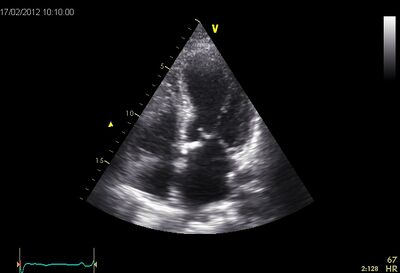

LVF slecht05.jpg

Dilated LV on PLAX